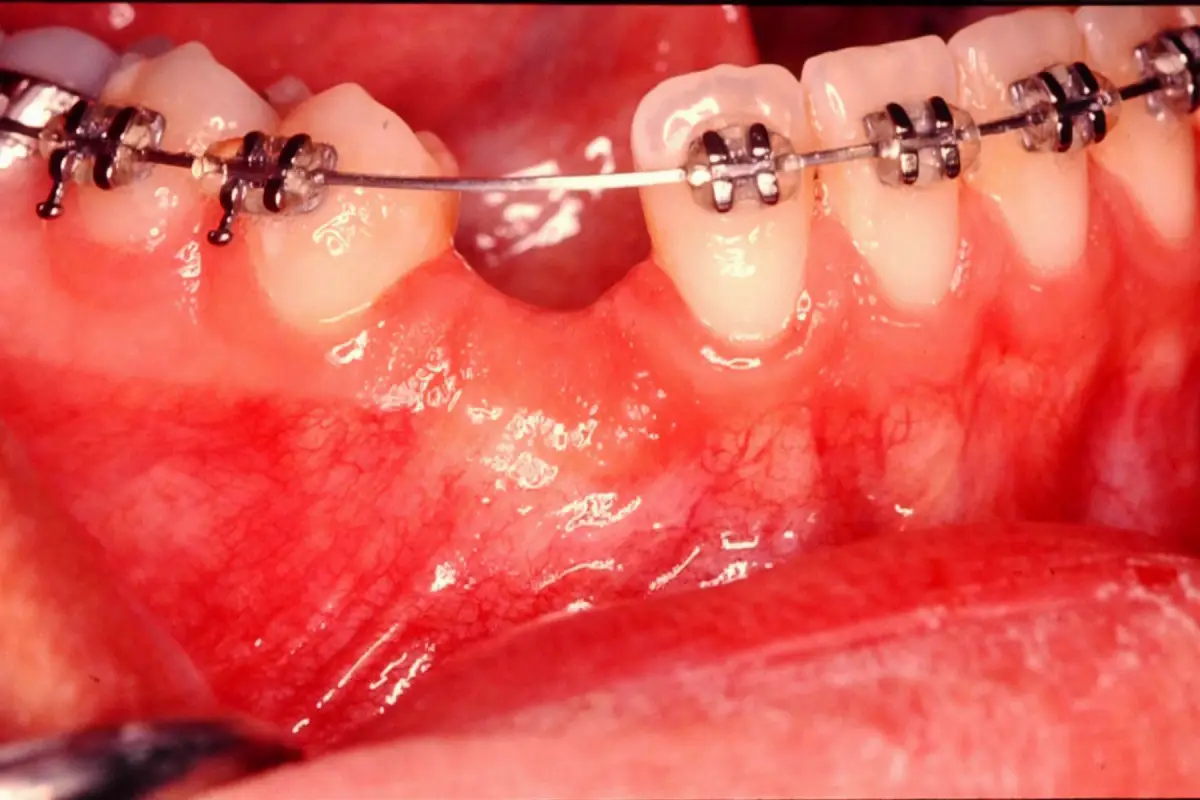

Ortho Exposure

before

after